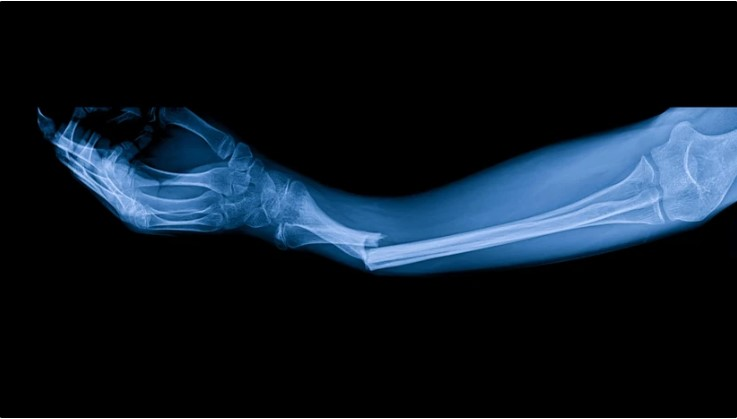

Cercetătorii chinezi anunţă o inovaţie medicală care ar putea revoluţiona tratamentele ortopedice/ Un adeziv osos capabil să repare fracturile în doar câteva minute!

Echipa de specialişti din provincia Zhejiang, condusă de dr. Lin Xianfeng de la Spitalul Sir Run Run Shaw, a dezvoltat un compus inovator numit „Bone-02”, care permite lipirea fragmentelor osoase în aproximativ trei minute, fără a fi nevoie de implanturi metalice sau intervenţii chirurgicale invazive.

Primele teste de laborator şi studiile clinice au confirmat eficienţa şi siguranţa substanţei. În cadrul experimentelor efectuate pe peste 150 de pacienţi, „Bone-02” a demonstrat o forţă de lipire de peste 180 kg, depăşind parametrii mecanici ai implanturilor metalice convenţionale.